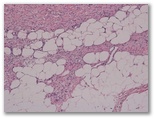

1332-R3-Neurofibroma

1. Neurofibroma